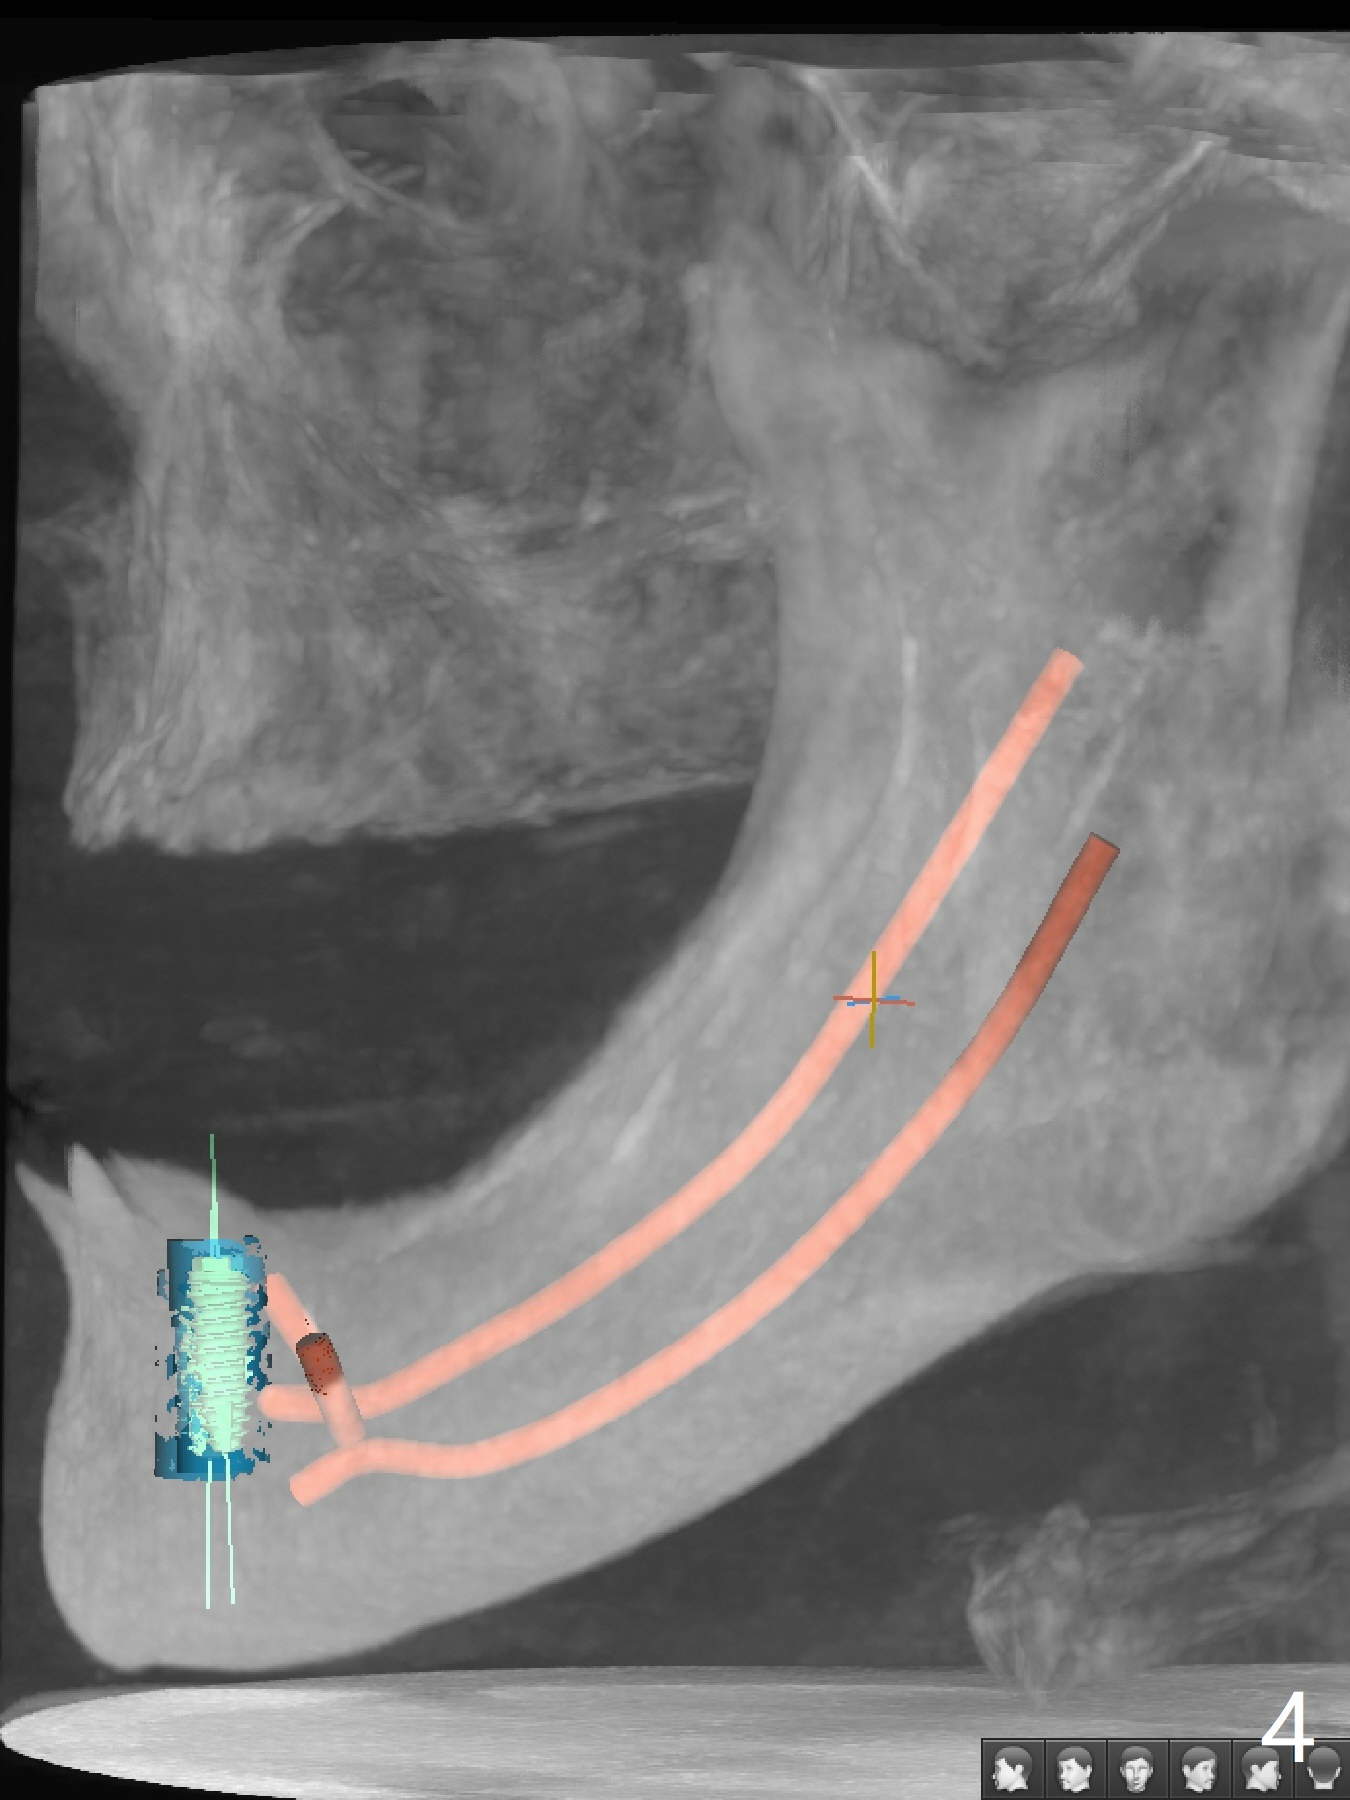

A 79-year-old woman is not pleased with cross bite and no tooth exposure of the upper complete denture (Fig.1-4). Her immediate concern is the loose lower RPD (Fig.5) after loss of the tooth #21 (Fig.6). The tooth #22 has mobility II. SM narrow implants will be placed at #22 and 27 immediately after #27 extraction (Fig.7,8). Ball abutments are going to be inserted prior to soft reline of the lower RPD. Prepare an acrylic bur to make a receptacle in the RPD for #27 abutment and high speed handpiece to section the tooth #22 as a denture tooth (prepare hard pink acrylic)